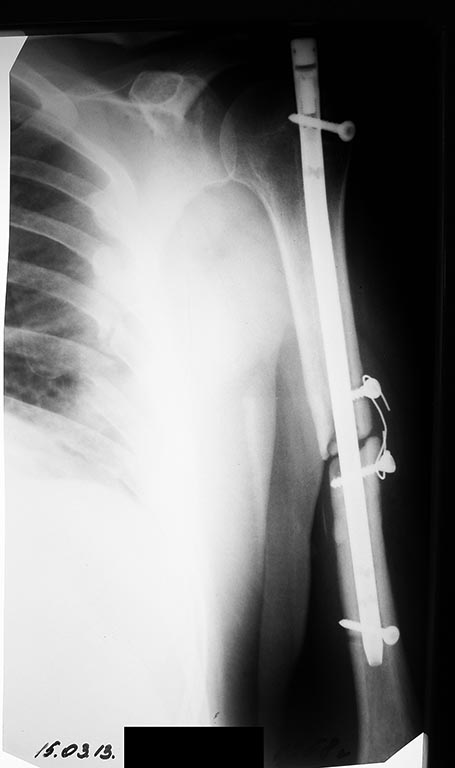

Травма 25.09.2012. 27.09.2012 - Остеосинтез левого плеча стержнем Кюнчера. Воспалительных реакций после операции не было.

Через 3 мес - 25.12.2012 повторная операция - Остеосинтез левого плеча стержнем с блокированием. Воспалительных реакций после операции не было.

Поступил в травматологическое отделение Госпиталя с жалобами на: сохраняющуюся слабость в левой верхней конечности. Общие анализы крови и мочи спокойные (эр - 4,7; Тромб - 284; Лейк - 5,1; сегм - 55; лимф - 36; СОЭ - 6).

Планируется удалить конструкции, установить чрескостной спицевой аппарат.